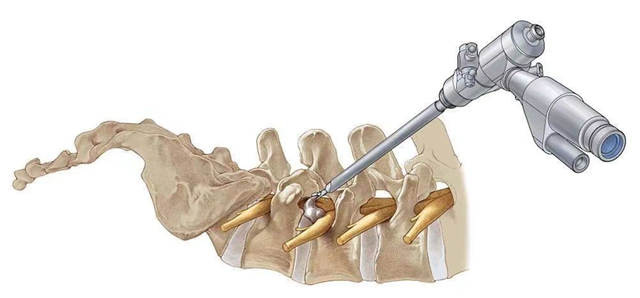

什么是椎间孔镜手术?

椎间孔镜与脊柱内窥镜类似,是一个配备有灯光的管子,它从病人身体侧方或者侧后方进入椎间孔,在安全工作三角区实施手术。在椎间盘纤维环之外做手术,在内窥镜直视下可以清楚地看到突出的髓核、神经根、硬膜囊和增生的骨组织,然后使用各类抓钳摘除突出组织、镜下去除骨质、射频电极修复破损纤维环。

手术创伤小,皮肤切口仅7mm,如同一个黄豆粒大小,出血不到10ml,术后仅缝1针,是同类手术中对患者创伤最小、效果最好的椎间盘突出微创疗法。